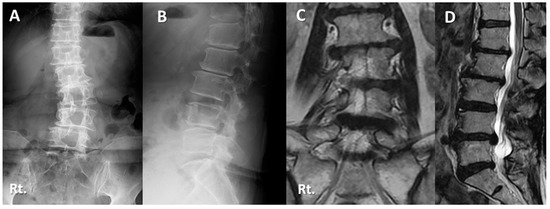

Case Presentations